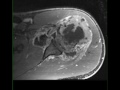

Giant Cell Tumor, Humerus

53-year-old female who presents for chronic left shoulder pain. There is an infiltrative proton density isointense, STIR hyperintense, diffusion restricting and heterogeneously enhancing mass involving the proximal left humerus. There is a complex left shoulder effusion with heterogeneous enhancement. The tumor extends to the proximal left humeral epiphysis. Differential diagnosis includes giant cell tumor, chondroblastoma, chondromyxoid fibroma, metastatic disease and plasmacytoma. On biopsy, this was found to be a giant cell tumor. Giant cell tumors are relatively common benign tumors which are found arising from the metaphyseal regions with extension to the physis of long bones. The peak between 20-30 years of age with a slight female predilection. Presentation is usually insidious and related bone pain, soft tissue mass, compression of surrounding structures and possibly pathologic fracture. Lesions more commonly occur in the distal femur, proximal tibia, distal radius, sacrum and vertebral bodies. Treatment is with curettage and packing.